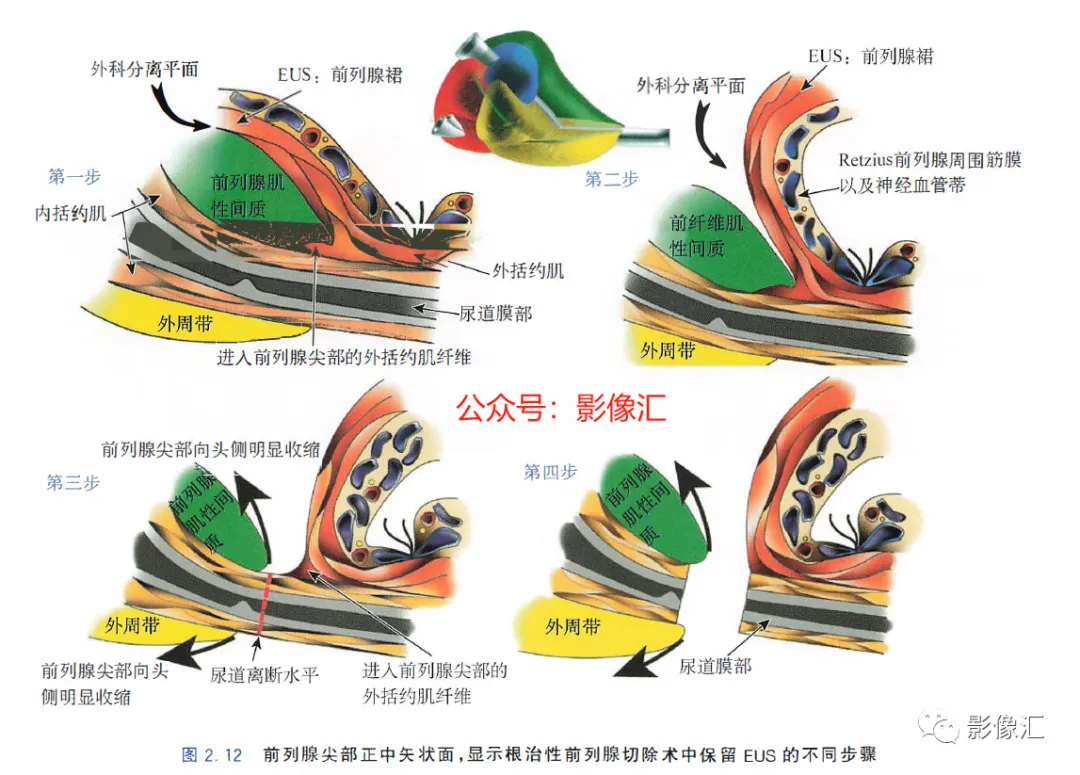

前列腺尖部是用于表示前列腺腺体尾侧(最下方)的术语,与尿道膜部密切接触。前列腺尖部可显示出不同的形态:圆环形或腹侧,背侧或两侧突出(图2. 9和图2.10) ,了解前列腺尖部形态的重要性主要在于两点:(1)前列腺尖部或多或少与EUS(尿道膜部的横纹肌纤维)头侧区域重叠(或覆盖),这些纤维部分融入前列腺尖部(图2.11)。在接受根治性前列腺切除术的患者中,有必要采用能够外翻(exteriorising)和解剖这部分横纹肌纤维的手术技术, 以保持控尿功能(图2.12)。(2)在根治性前列腺切除术中必须避免阳性边缘 。值得注意的是,在尖部水平,腺体组织仅为外周带组织,尖部仅前缘一小部分为AFMS。此外,前列腺尖部构成所谓的梯形区域的顶部,这是众所周知的解剖薄弱区域,在该区域前列腺癌可更易侵犯至前列腺间隙(图2.8)。在其前外侧,前列腺尖部由外括约肌群覆盖,与AFMS及从膀胱颈延伸来的由平滑肌构成的逼尿肌群相融合(图2. 13)。前列腺尖部尾侧与尿道膜部起始部相延续。男性的尿道膜部被认为是位于前列腺尖部和尿道球部之间的尿道部分,长度约为1cm。其内有尿道内括约肌(IUS)和尿道外括约肌(EUS)。IUS从膀胱颈(此处最厚)延伸到尿道球部,沿尾侧方向厚度逐渐减小。IUS环尿道膜部,由双层平滑肌纤维组成,包括内层纵行肌和外部的环形肌(图2. 13和图2. 14)。IUS的神经支配来自自主神经、交感神经和副交感神经系统。下腹下神经丛负责前列腺、前列腺尖部和尿道膜部的所有自主神经支配。其终末支沿内侧走行达耻骨上肌,外侧走行达尿道膜部的EUS,在腹侧构成所谓的阴茎海绵体神经(负责勃起机制)和尿道海绵体神经(负责尿道膜部黏膜的自主神经传入,直接与控尿机制有关(图2 . 13 和图2. 14)。EUS构成横纹肌平面(横纹肌纤维),在尿道膜部水平围绕IUS,在前列腺尖部的前外侧上扩展,并在该水平上构成所谓的EUS围裙(图2. 13)。其肌纤维主要是I 型(即没有肌梭),尽管强度低,但专门负责长时间收缩。EUS的功能在于排尿间期保持尿道腔塌陷,从而防止无意识的尿液渗漏。EUS最厚处位于尿道膜部水平,厚度向头侧逐渐减小,最终构成前列腺围裙。该围裙以Ω(希腊字母“欧米伽”)形围绕尿道膜部,而后正中不包绕, 形成“后正中脊”(图2. 13 和图2. 14)。此外,EUS的部分横纹肌纤维融入到前列腺尖部的下部,位于精阜下方,融入纤维的多少依赖于前列腺尖部形态(图2. 11) 。EUS的神经支配和动脉供血分别来自外阴神经和外阴内动脉。该神经为躯体神经,因此EUS可随意控制。外阴内神经和动脉均向头侧走行,至会阴深横肌处,发出分支支配EUS最尾侧部分,随后形成阴茎背侧神经脊背侧动脉。前列腺尖部与支配EUS的外阴内动脉的分支之间距离为3~13mm (图2. 13)。IUS和EUS构成所谓的控尿被动及内在因素。它们的功能基本上是“塌陷”尿道至“后正中脊”,这样可防止排尿间期无意识的尿液“泄露”(图2.11和2.13)。阴茎海绵体神经在前列腺周围筋膜的后外侧及前外侧走行。手术操作时保留这些外侧神经对于确保前列腺根治术后勃起功能的恢复是至关重要的。会阴体是一纤维肌性结构,难以在解剖上进行评估,其功能是支持所有构成会阴部及支撑盆腔脏器的肌肉及腱膜结构。对于控尿,会阴体形成一固定的底盘,通过将EUS的横纹肌平面压至底盘处,从而可使EUS正确发挥功能,这样在排尿间期可以正确地使尿道塌陷。会阴体由以下结构组成(图2.13)和图2.14)。

根治性前列腺手术有两个主要目标:完全切除肿瘤和令人满意的术后功能,即控尿及阴茎勃起功能的恢复。为了在根治性前列腺切除术后实现早期控尿恢复,需要完全保留尿道括约肌系统,同时保留耻骨直肠肌和耻骨会阴肌(后者更为重要)。EUS的保存始于在腺体顶端前外侧上彻底分离EUS裙,向尾部方向操作。根据尿道周围筋膜,可正确识别和分离尿道膜部的EUS,这是阴茎海绵体和尿道海绵体神经未梢的位置(图2.12 至图2.14) 。AFMS和前列腺尖部的MRI评估可以显示这些区域中存在肿瘤,或者为主要病灶区域,或者更常见的是,MRI可以显示最初其他解剖区域的肿瘤对AFMS和(或)前列腺尖部的局部累及。这些情况下,在这个水平由于造成阳性切缘的风险很高,因此括约肌保留手术是禁忌的。